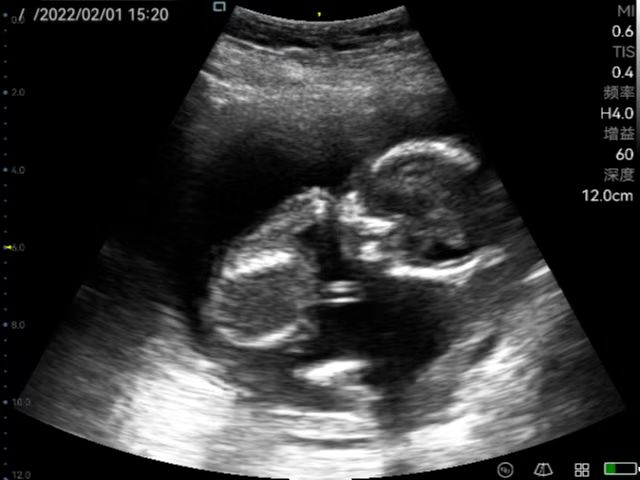

Taking obstetric screening in basic medical care as an example, P50 can accurately screen fetal development anytime, anywhere.

General practice use (mainly divided into ultrasound diagnostic systems for cardiovascular, abdominal, superficial organs, fetus, abdominal large blood vessels and limb blood vessels. Superficial organs mainly include diseases of thyroid, breast, eye, testis, scrotum, etc. Generally, high-frequency probes are used. Abdominal organs are mainly divided into digestive system, urinary system, gynecology, including uterus, accessories and other diseases. Fetal diagnosis in normal fetuses in the early, middle and late stages, mainly observe fetal growth and development, examination of Amniotic fluid, umbilical cord, placenta. Vascular ultrasound diagnosis, including carotid artery, abdominal large blood vessels and blood vessels of limbs, to know whether there is plaque and stenosis in arteries, and whether there is thrombus in veins; for the heart, mainly detect whether there are abnormalities in intracardiac structure and hemodynamic changes.), remote diagnosis.